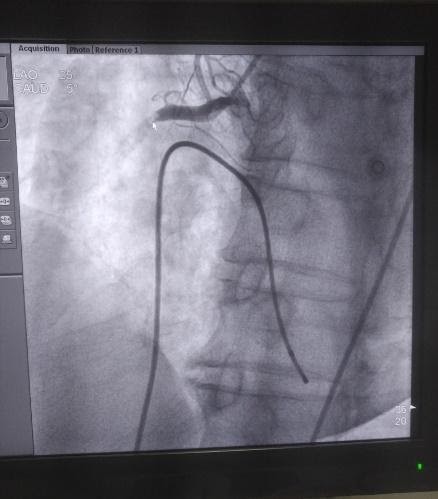

Hình ảnh huyết khối gây tắc cụt động mạch vành phải từ đoạn I. Ảnh: Bệnh viện Đa khoa Đức Giang |

Trước tình hình đó, các bác sỹ đã thảo luận nhanh và đưa đến chẩn đoán bệnh nhân bị ngừng tuần hoàn do nhồi máu cơ tim cấp, cần can thiệp cấp cứu. Sau 45 phút, ca can thiệp thành công, huyết áp bệnh nhân được kiểm soát tốt.